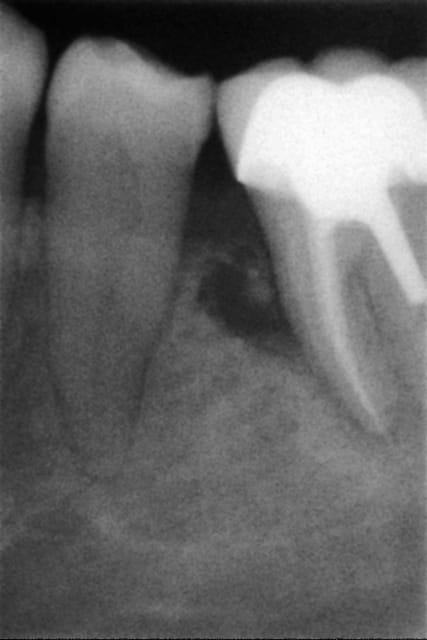

Je vous fais passer la radio qui montre une image au niveau du septum 35 36 et je suis vraiment étonné qu'en l'espace de si peu de temps je puisse avoir une telle lésion.

Je veux pas dire mais le dépassement en mésial a pourvu l'os en germe et on a une infection qui remontre depuis l'apex vers le haut, après un autre élément se surajoute, à voir du côté de ce qui a été écrit plus haut.

Merci pour vos avis,en grossissant la radio on peut effectivement penser à une fracture de la racine.Ce n'est pourtant pas la racine qui supporte le tenon.

Je suis quand même un peu dérouté par cet incident que je rencontre pour la première fois en 32 ans de cabinet,j'ai eu des fractures de racines sur des dents couronnées mais souvent après plusieurs années et en général sur les racines qui supportaient le tenon.

Certainement le traitement radiculaire a aggravé une fissure existante de la racine.